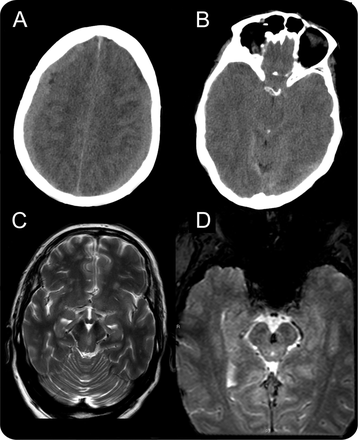

一个67岁的老人与心房颤动的临床历史和口服抗凝剂使用了头痛和呕吐,昏迷在几小时内迅速恶化。CT显示双边硬膜下血肿transtentorial疝和脑干压缩(图)。得到了双边磨洞。术后复苏的除了左前核间眼肌麻痹瘫痪的内收的左眼右外侧目光收敛与保存)。

图

成像

CT显示双边硬膜下血肿(A)和中部和uncal transtentorial形成疝与脑干压缩(B)。T2加权图像(C)显示了一个小区域的左侧中脑hyperintensity内侧内侧纵束和眼球运动的核,与敏工件T2 *图像(D),相应的含铁血黄素。

随后的核磁共振显示局部病变在中脑的中央部分解释为Duret出血(所示图)。一般来说,Duret出血被认为是严重的,往往致命的,大脑形成疝并发症,1然而,微妙的神经赤字,如核间眼肌麻痹,可能是它唯一的标志。